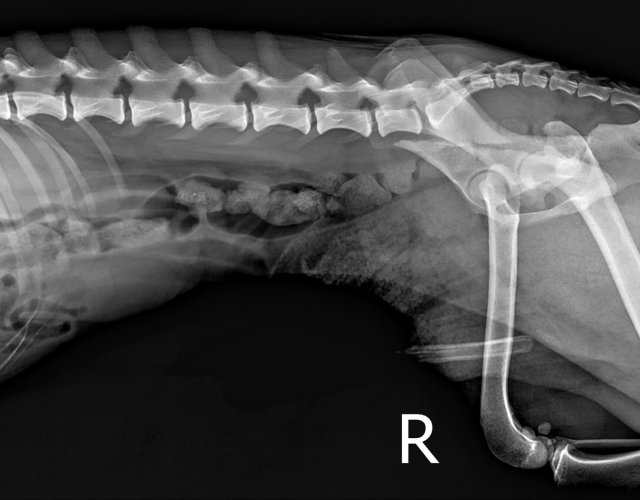

Caine accidentat

O doamna a gasit un caine lovit de masina si l-a tras pe marginea drumului pentru a suna peste tot in cautare de ajutor. Am raspuns pozitiv si am facut totul pentru el. Din pacate nu a putut fi salvat, decedand a doua zi dupa interventia chirurgicala. Foarte probabil din cauza unei embolii pulmonare. Le multumim celor care au donat. Medicul a anulat factura iar banii vor ajuta desigur alte animale de care ne ocupam zilnic.